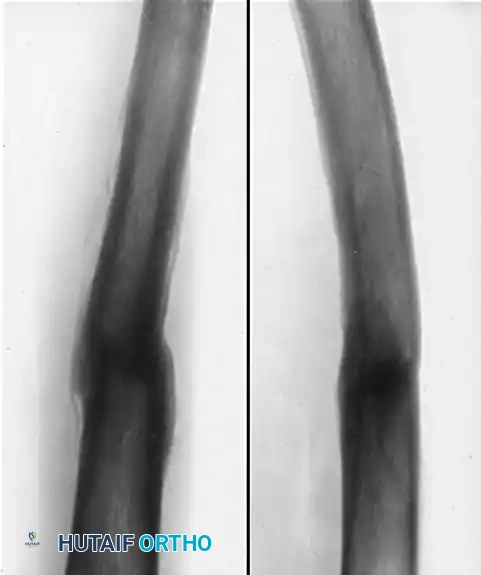

The following imaging demonstrates the natural history and surgical management of a severe pediatric femoral malunion.

Figure B: Radiographic appearance five months after open reduction and corrective osteotomy. The procedure involved the insertion of a Kirschner wire through the distal femur and the application of a spica cast incorporating the wire to maintain length and alignment. Through this intervention, the length of the limb and the functional mechanics of the knee were successfully regained, allowing subsequent growth to finalize the remodeling process.